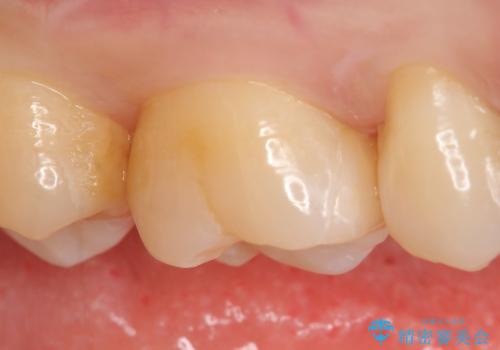

- 右上の奥歯で冷たいのもがしみるといらっしゃった方の症例です。

虫歯を除去後、セラミックインレーによる修復を行いました。

当院のセラミックインレーはemaxという強度と審美性に優れた材料を使用しています。

またプレス方式でインレーを製作しているため、削り出しで製作するCADCAMより優れた適合性も持ち合わせており、虫歯が再発しにくい修復物です。